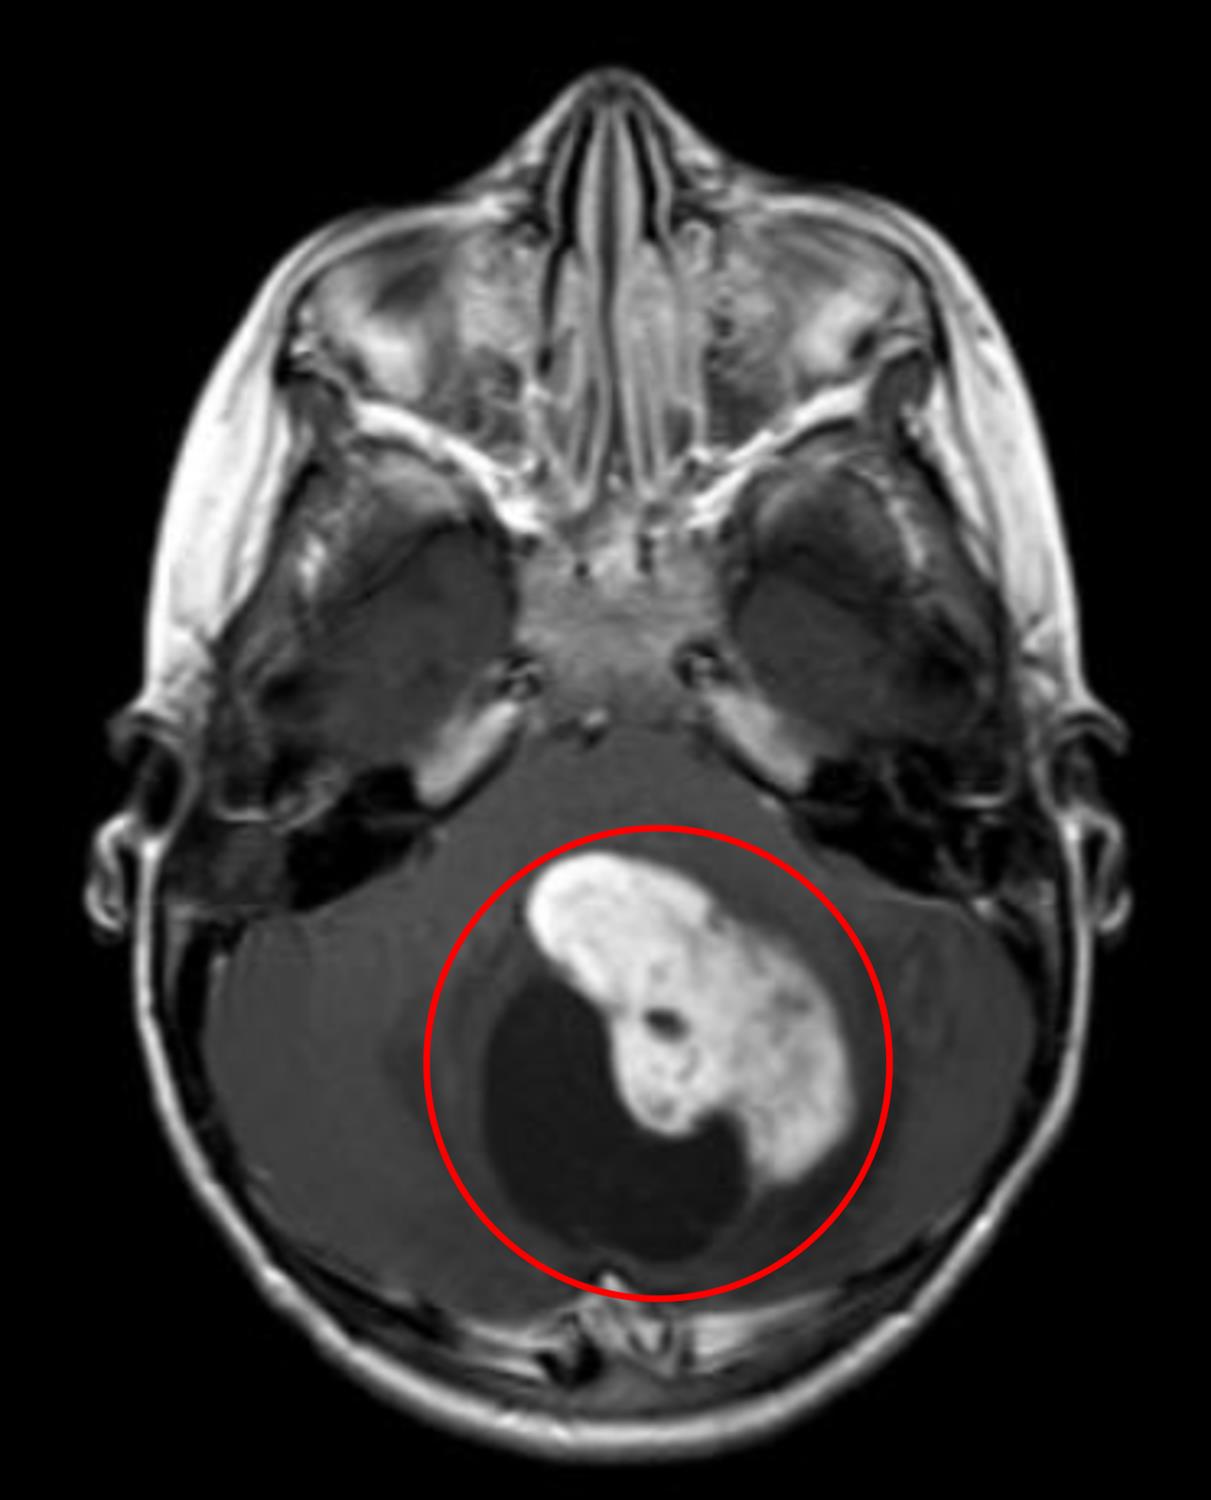

A 7-year-old boy is brought to his pediatrician by his mother with a 3 month history of headaches. His mother first started complaining of headaches after he had an upper respiratory infection. Since then, the patient has been having increasingly frequent headaches that are worse in the morning and when lying down. He has also had occasional nausea and vomiting. Over the past month, he has had increasing difficulty sitting upright and an unsteady gait. He has not had fevers or chills. He has no prior medical problems and takes no medications. His temperature is 98.6°F (37.0°C), blood pressure is 106/69 mmHg, pulse is 95/min, and respirations are 21/min. On examination, the patient has truncal ataxia and dysmetria on finger-nose-finger testing. Magnetic resonance imaging of the head is performed and the results are shown in Figure A. Which of the following findings would be expected on histopathologic examination of this patient’s lesion?

Figure/Illustration A is an MRI of the brain demonstrating a lesion with both solid and cystic components (red circle). These findings are classically seen in patients with a pilocytic astrocytoma.

This patient who presents with morning headaches worse with lying down, ataxia, dysmetria, and a cerebellar lesion with both solid and cystic components most likely has a pilocytic astrocytoma. A histopathologic examination of these tumors would show eosinophilic, corkscrew fibers known as Rosenthal fibers.

Pilocytic astrocytomas are low-grade astrocytomas that are the most common primary brain tumor in childhood. Pilocytic astrocytomas can be associated with neurofibromatosis type 1, but may also arise sporadically. In idiopathic settings, it is usually associated with mutations in the mitogen-activated protein kinase pathway. These tumors are most often found in the cerebellum and can present with signs of hydrocephalus, seizures, and cerebellar signs. On neuroimaging, these tumors usually have both cystic and solid components. As these tumors are generally circumscribed and rarely invasive, surgical resection is the standard treatment. Radiation therapy and chemotherapy are usually reserved for recurrence.

Pilocytic astrocytoma has both solid and cystic components and will show eosinophilic corkscrew fibers on histopathology.